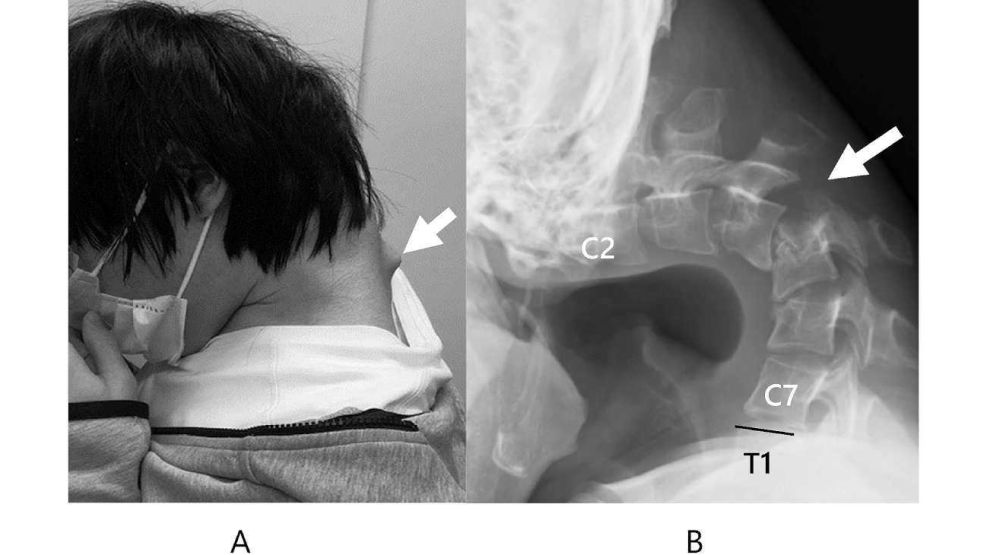

Al respecto, señalaron que la fuente del problema fue estar horas jugando frente al dispositivo: "Se sospechó que la etiología de esta cifosis cervical se debía a una combinación de un trastorno del desarrollo subyacente y posturas de flexión cervical habituales y prolongadas al jugar con teléfonos inteligentes". De esa manera, desarrolló un bulto a lo largo de su nuca, atribuido a que sus vértebras se "extendieron extremadamente" por la posición antinatural. En ese sentido, se habían distorsionado y dislocado. Al no haber recibido tratamiento, con el paso del tiempo se había desarrollado tejido similar a una cicatriz en la columna.

En su lugar, optaron por realizar cirugías combinadas. A través de ese método, le quitaron pequeños segmentos de sus vértebras y parte del tejido cicatricial que se había desarrollado. Luego, le insertaron una serie de tornillos y varillas de metal en los huesos para corregir su postura. Seis meses después, pudo mantener la cabeza en posición horizontal y, durante el año siguiente, no volvió a presentar problemas para levantar la cabeza o tragar. "Las cirugías combinadas anterior y posterior obtuvieron buenos resultados y mejoraron notablemente la calidad de vida del paciente", subrayaron los médicos.